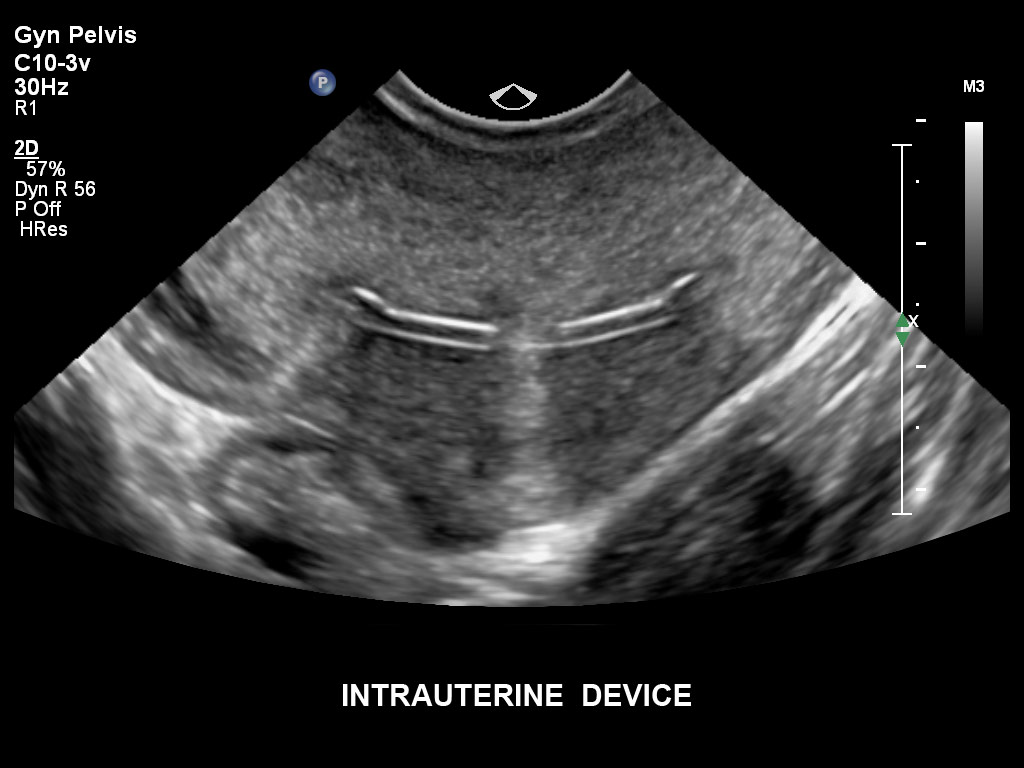

Überzeugende Bildgebung in allen Schwangerschafts­dritteln

Die EPIQ-Produktreihe mit ausgereiften Schallköpfen erfüllt die Anforderungen auch Ihrer anspruchsvollsten gynäkologischen Untersuchungen und während der gesamten Schwangerschaft.

• C10-3v PureWave-Breitband-Endo-Convex-Schallkopf, ideal für anspruchsvolle Myom- und komplexe Ovar-Untersuchungen sowie Bildgebung im ersten Schwangerschaftstrimester